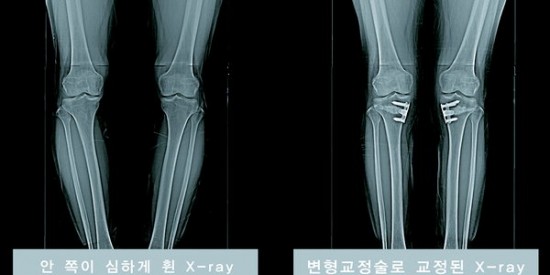

이 때는 무릎안쪽 연골에 실리는 부담을 바깥으로 덜어주는 ''변형교정술''이 효과적이다. ''변형교정술(근위경골외반절골술)''은 종아리뼈(경골)를 바로잡아 안쪽 관절에 실리는 부담을 골고루 분산시키는 원리다.

반면 개방형은 합병증이 적고 추후 인공관절 수술이 쉬운 편이다. 종아리 안쪽 뼈 사이 간격을 벌려 인공뼈를 넣고, 나사로 고정하는 치료법이다.

''변형교정술''에서 가장 중요한 것은 골반뼈부터 무릎, 발목을 잇는 다리 축을 정하는 일이다. 이상적인 각도는 대퇴골과 무릎, 발목관절이 일직선을 유지하는 것이다.

과거 육안으로 각도를 측정하던 것과 달리, 최근 내비게이션을 이용해 컴퓨터로 수치를 계산하므로 정확도와 성공률이 높다. 시술 시간은 약 40분이며 한달 정도 회복기간이 걸린다.